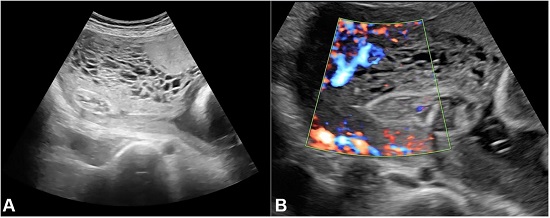

The patient did not attend the scheduled consultations at the antenatal clinic and presented again at 26 weeks’ gestation. There were no complaints of repeated episodes of vaginal bleeding. As the 16-18 weeks anomaly scan was missed, she was sent for an ultrasound to check on fetal anomalies. The ultrasonography (USG) report revealed the following findings: (i) a single intrauterine fetus with fetal heart frequency of 138 beats per minute; (ii) a mean gestational age of 25weeks 3days(determined by biparietal diameter, femur length, abdominal circumference, and head circumference); (iii) the expected birth weight of the fetus was 928 g; (iv) the amniotic fluid volume was in the normal range for the gestational age; (v) there was no gross congenital anomaly in the fetus; (vi) the placenta was conspicuous with a focal thickening in the right lateral aspect measuring 93×50 mm; (vii) the abnormal area of placenta showed multiple hypoechoic/cystic areas with some blood flow on Doppler study (Figure 1).

Figure 1

Ultrasound showing placenta with the cystic area.